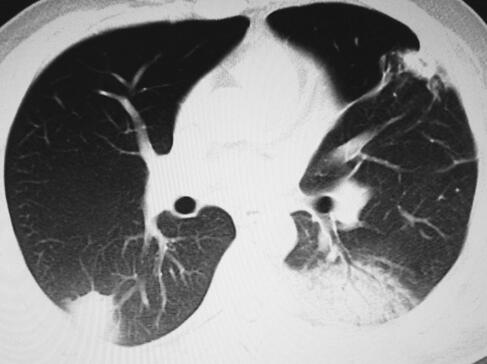

诊治经过:入室后给予吸氧监护,抽血培养,每小时1次,共抽3次血培养后开始经验性抗感染治疗。选用万古霉素+阿米卡星联合治疗,以及其他输液支持对症治疗。患者体温、症状、氧合以及一般情况仍无好转,第3天将阿米卡星换为亚胺培南-西司他汀钠。第4天因患者储氧面罩吸氧时氧合在90%左右,给予患者经口气管插管接呼吸机辅助通气,氧浓度50%+PEEP 10cmH2O的条件下可维持指氧93%左右。多次经气管插管吸痰送检细菌、真菌、结核涂片、培养均阴性,5次血培养结果均阴性,抽血查免疫全套、肿瘤标志物全套均阴性,复查床旁胸片提示双肺多发渗出(图3)。

图3 胸部X线片示双肺多发渗出